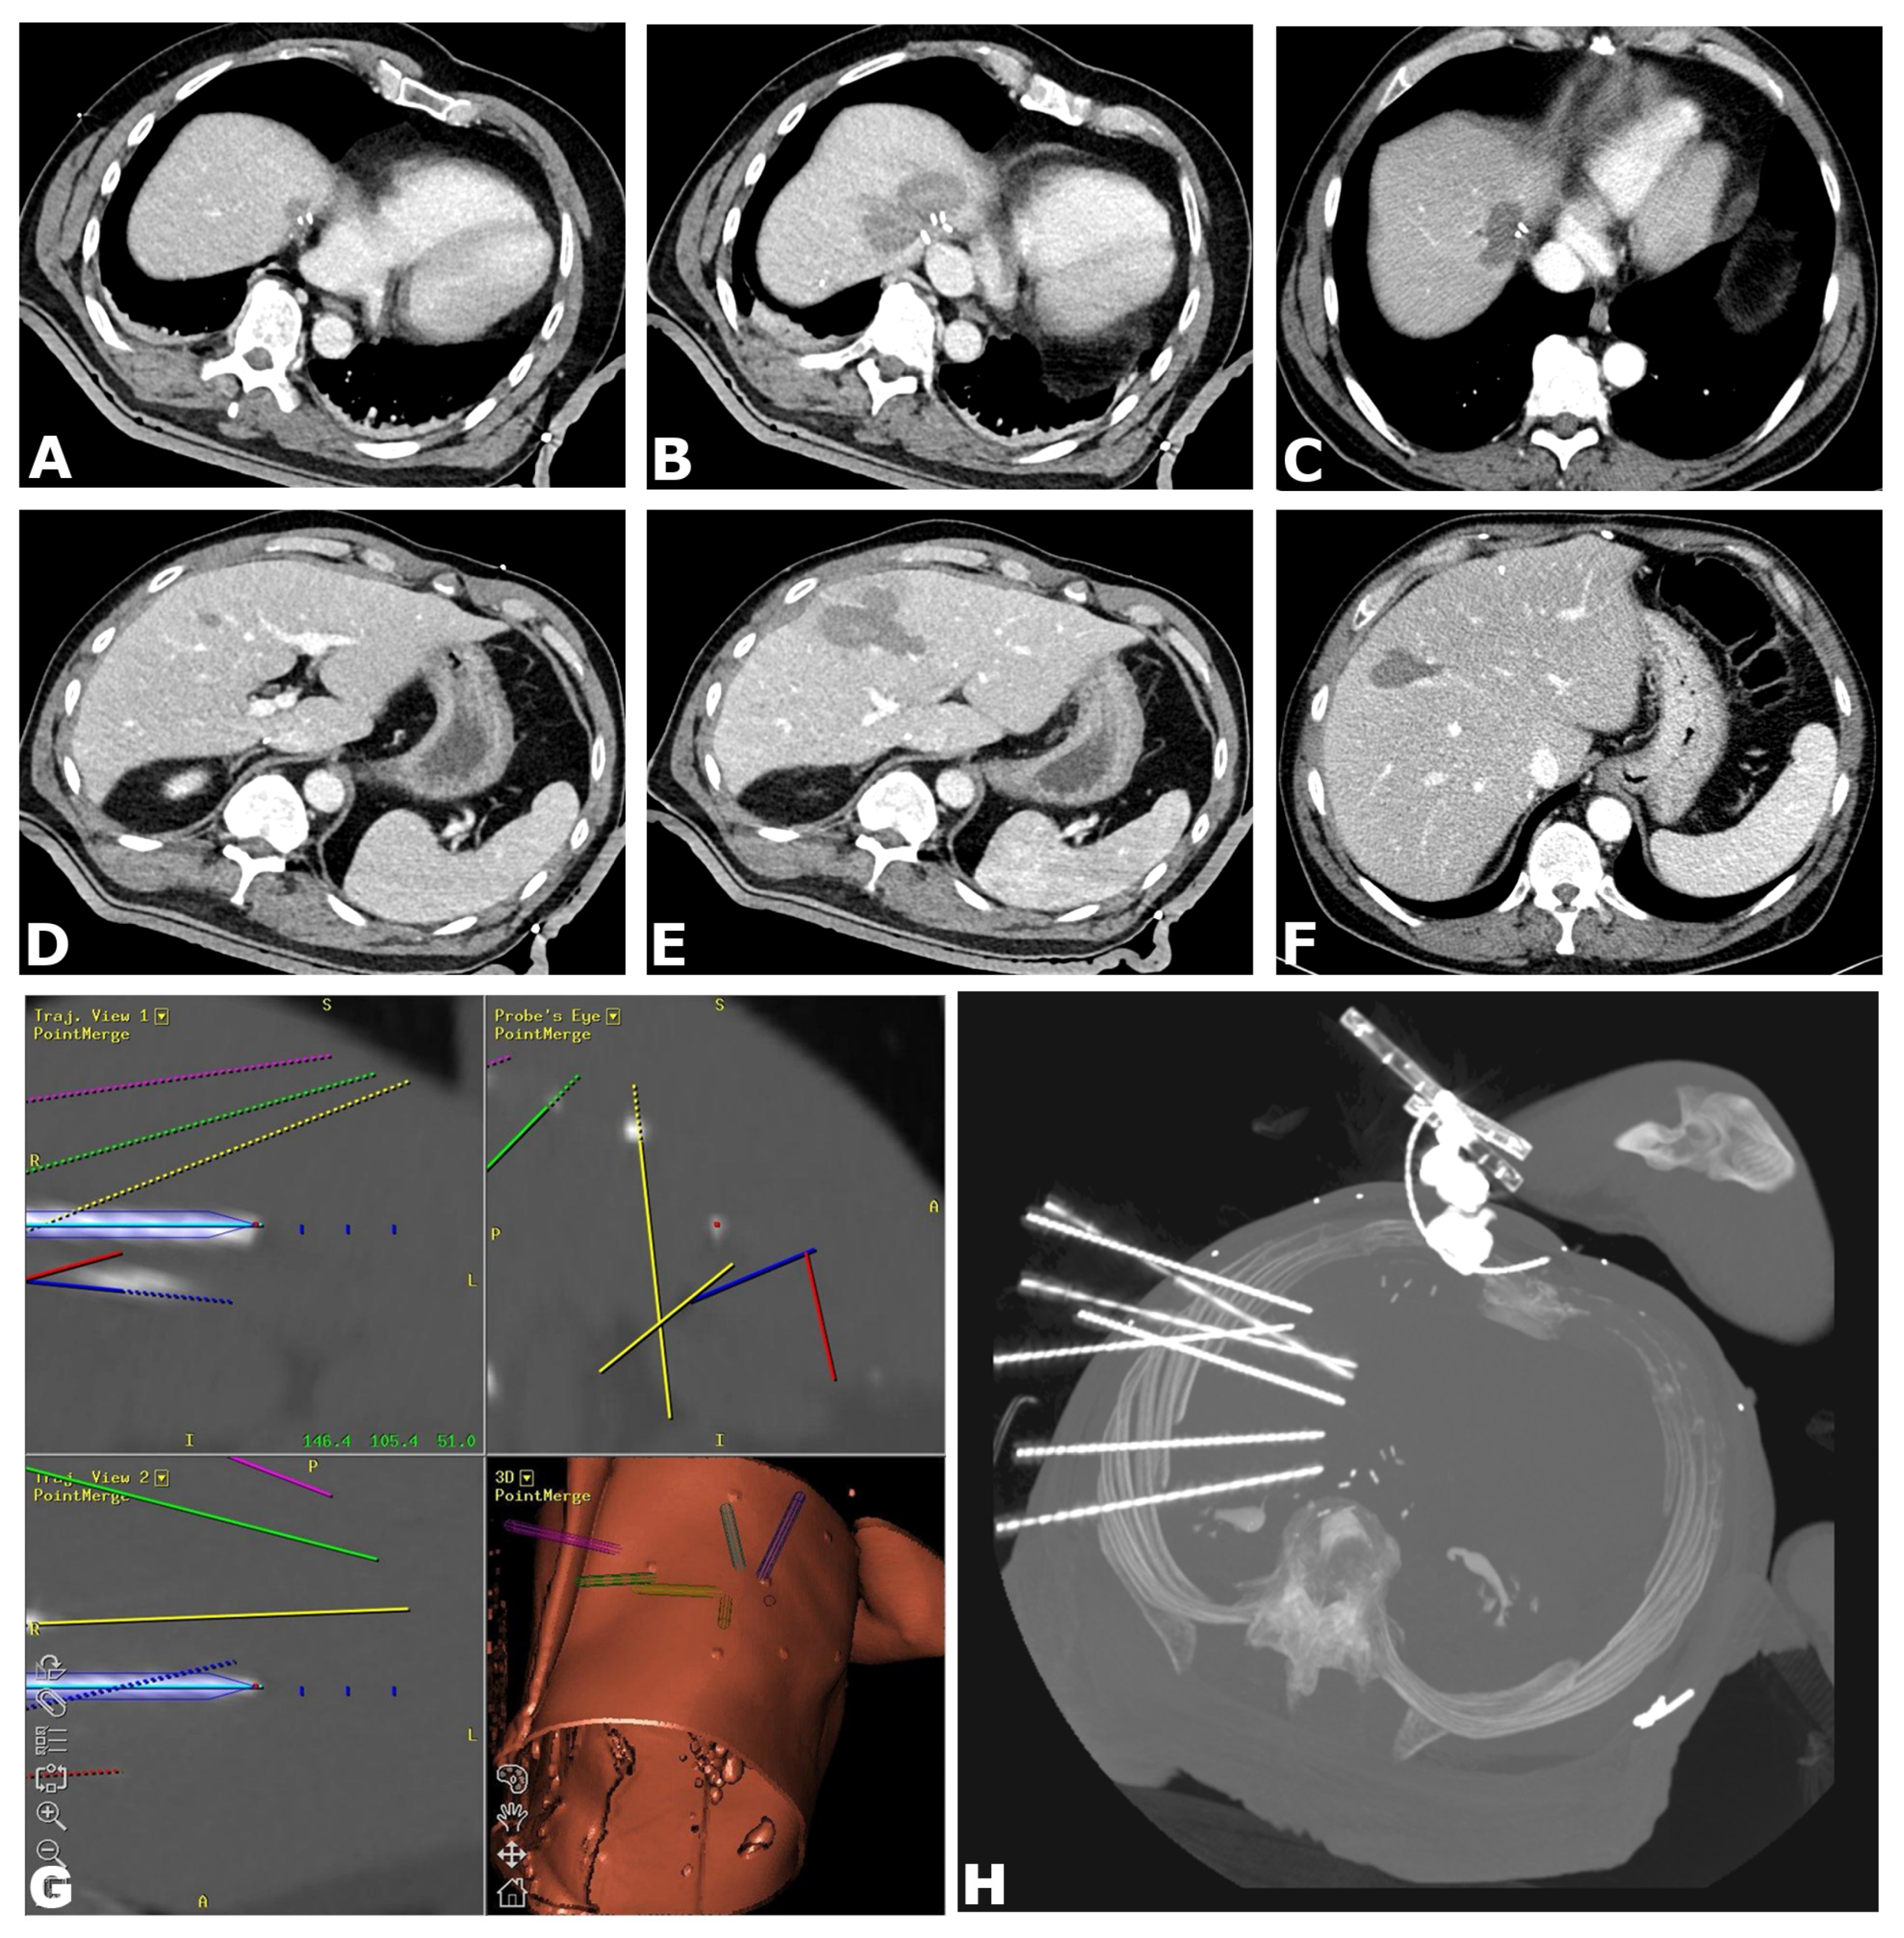

- Preparation: The entire procedure is carried out under general anesthesia with full muscle relaxation. Immobilization is provided by a single (Bluebag, Interventional Systems, Kitzbühel, Austria) or double vacuum fixation technique (BodyFix, Medical Intelligence, Schwabmünchen, Germany). For image-to-patient registration, 10–15 registration markers (Beekley Spots, Beekley Corporation, Bristol, CT, USA), are broadly attached to the skin.

- Planning: A contrast-enhanced CT scan is acquired (Siemens SOMATOM Sensation Open, 82 cm bore size diameter, sliding gantry, Siemens AG, Erlangen, Germany) with 3 mm slice thickness in arterial and portal-venous phases. Datasets are transferred to an optical navigation system (Stealth Station Treon plus, Medtronic Inc., Boulder, CO, USA) and one or multiple antenna trajectories are planned with multiplanar and 3D reconstructed images using the navigation systems’ software.

- Needle Placement: To compensate for respiratory motion, temporary disconnections of the endotracheal tube (ETT) are carried out during each CT scan and for needle placement. After registration and sterile draping, an ATLAS aiming device (Interventional Systems, Kitzbühel, Austria) is used for navigated trajectory alignment and the placement of 15G/17.2 cm coaxial needles (Bard Inc., Murray Hill, NJ, USA) without real-time imaging control, serving as guides and placeholders for the RF electrodes. After co-axial needle placement, a non-enhanced CT-scan is acquired to verify needle placement by image fusion with the planning CT scan using the navigation system’s image 3D registration algorithm.

- RF Ablation: Up to three 17G RF probes (Cool-tip, Medtronic, Boulder, CO, USA, 3 cm exposure, 25 cm length) are inserted through the coaxial needles for serial tumor ablation, using the unipolar Cool-tip RF generator (Cool-tip, Medtronic, Boulder, CO, USA) and the Cool-tip RF switching controller for RF ablation. The standard ablation time for three RF probes is 16 min or until a significant increase in impedance (“roll-off effect”) is observed. Needle track ablation is performed prior to repositioning and final removal to reduce bleeding and potential tumor seeding.

- Finalization: After ablation, a final contrast-enhanced CT scan is carried out in both arterial and portal venous phases for the assessment of complications and evaluation of the ablative safety margins in 3D. If needed, the intervention may be continued in the same session by additional placement of coaxial needles and subsequent ablation (e.g., residual tumor, lack of sufficient safety margin).